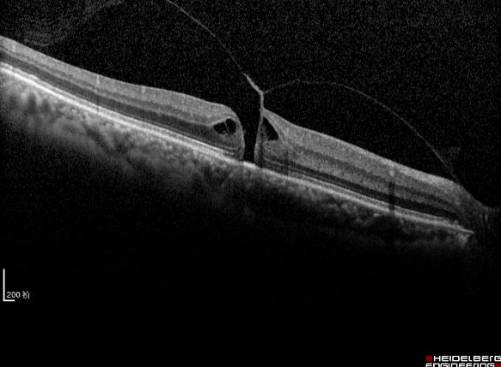

黄斑裂孔

随着年龄的增加,玻璃体浓缩、凝聚,玻璃体后界面与视网膜表面发生不同程度的后脱离。在脱离的过程中,由于在黄斑区域两者结合十分紧密,局部玻璃体黄斑牵拉,导致粘连的视网膜组织被撕脱下来,就形成了黄斑裂孔。因年龄造成的黄斑裂孔常无明确可循的原因,称为特发性黄斑裂孔。其他常见的原因还有外伤或高度近视等。黄斑裂孔一旦形成,会严重影响视力,应及时采取玻璃体手术封闭裂孔,可以有效阻止视力的进一步下降,术后视力提高的病例临床也不少见(见图8和图9)。

玻璃体手术采用局部麻醉、术中无痛感。具体手术方法主要行玻璃体切除术后,切除黄斑区粘连的玻璃体,解除玻璃体黄斑牵拉,同时撕除裂孔周围的视网膜内界膜,封闭裂孔。术中有可能在玻璃体腔内填充气体,通过气泡的顶压作用促进裂孔愈合。极少数特殊患者,需要填充硅油。如果患者合并白内障,联合超声乳化白内障手术,植入合适的人工晶体,术后视力更令人满意(见图8和图9)。

目前黄斑手术进入了微创时代,手术创伤更小、效果更确定、患者几乎无痛苦。通过手术治疗,裂孔封闭率达到90%以上。当然,手术成功率与术后视力恢复情况主要取决于病程长短、裂孔大小、牵拉的程度范围,尤其是术者的手术技巧。黄斑手术联合白内障手术,术后有的患者视力可达到0.8以上。